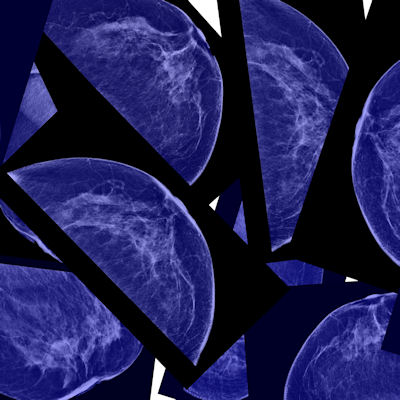

“Screening mammography is our No. 1 defense in detecting and addressing breast cancers at their earliest, most treatable stages, but it is also very important for people to be familiar with the look and feel of their own breast tissue so that sometimes subtle changes can be evaluated quickly to give us the best chance at early detection,” Pariser said in a statement.

While advances have been made in recent decades for breast cancer diagnosis and treatment, the disease still presents as a persistent challenge in women’s health. In 2023 alone, medical societies and organizations updated their recommendations for breast cancer screening, though they aren’t uniform.

For example, the American College of Radiology recommends that all women undergo a breast cancer risk workup by the age of 25 while reiterating that women should begin annual mammography at age 40. The U.S. Preventive Services Task Force meanwhile recommends biennial screening with mammography beginning at age 40 for all women, a B-grade recommendation.